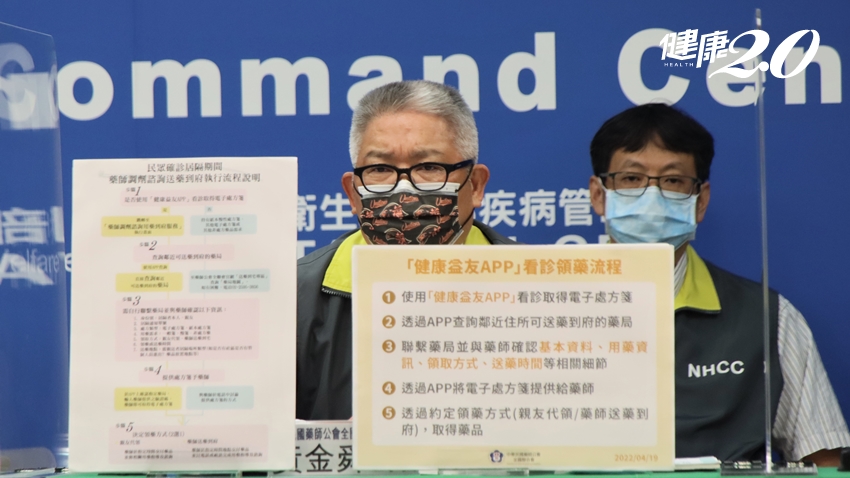

北醫附設醫院醫務部主任陳錫賢指出,快篩陽經診斷即確診實施後,不少民眾忘記攜帶快篩陽性的卡匣到醫院,希望以照片證明自身快篩陽性。不過,陽性卡匣必須經過醫師判讀後現場銷毀,才能完成判讀手續,因此無法利用照片證明,提醒民眾務必攜帶陽性卡匣到醫院,避免影響判讀程序。除此之外,北醫附醫也將第一線看診經驗彙整15大QA提供民眾參考。

Q:完成通訊診療後該如何領藥?

使用北醫附醫通訊診療者,可委託家人攜帶確診者健保卡,前往北醫附醫第三醫療大樓吳興商圈入口處遠距領藥櫃檯繳費並領藥。

Q:確診陽性隔離中,該如何領取藥物?

確診隔離中民眾有用藥需求,可使用通訊診療門診或確診用藥代領門診。